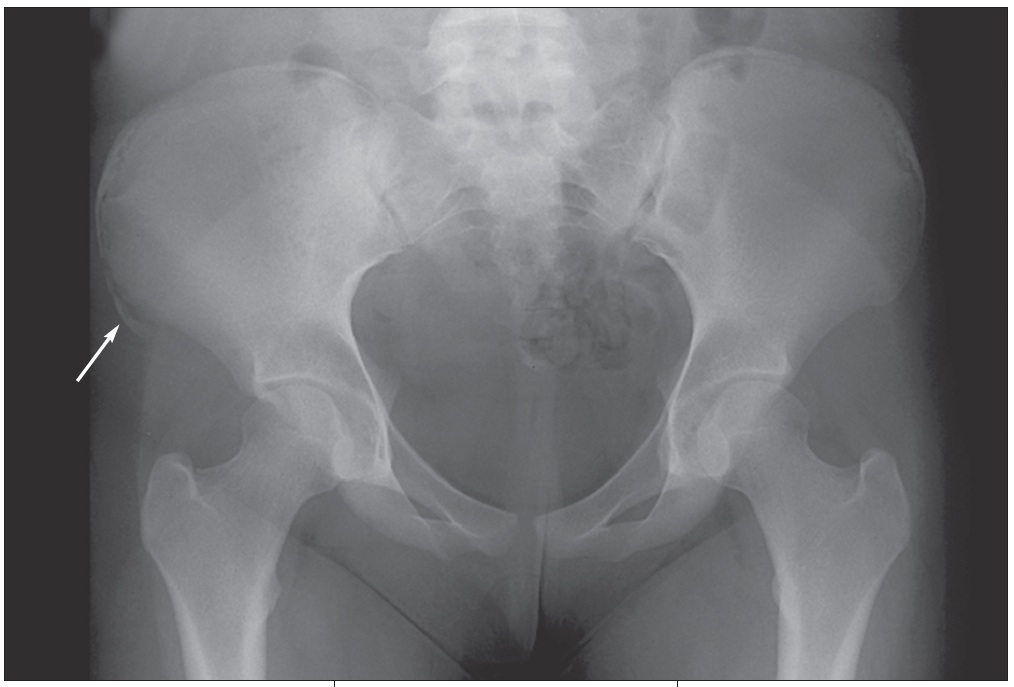

The patient was taken to the local emergency department (ED) immediately after her injury, where she was told that her pain was caused by a severe muscle sprain. She was sent home with analgesics. Her mother later received a call from the emergency department physician who told her that a radiologist had viewed the x-ray films and had diagnosed an avulsion fracture (Figures). The ED physician recommended a bone scan to rule out decreased bone mineral density "because young girls should not get hip fractures."

Fractures of the extremities occur frequently, but involvement of the trunk and pelvis--as in the case of this patient--is uncommon. An avulsion fracture of the pelvis occurs when a muscle contracts very forcefully, pulling off a piece of bone where the muscle and tendon connect. This fracture seldom occurs in children younger than 12 years but is particularly common in teenaged athletes.3 Groin injuries occur in 5% to 9% of high school athletes from a sudden acceleration-deceleration or directional change during sporting events.3

The treatment of trampoline mishaps is injury-specific. In our patient's case, an orthopedic consultation was obtained. The orthopedist agreed with the diagnosis of avulsion fracture based on the radiographic findings and did not recommend a bone scan. Rest and symptomatic relief were prescribed, and the fracture was allowed to heal.